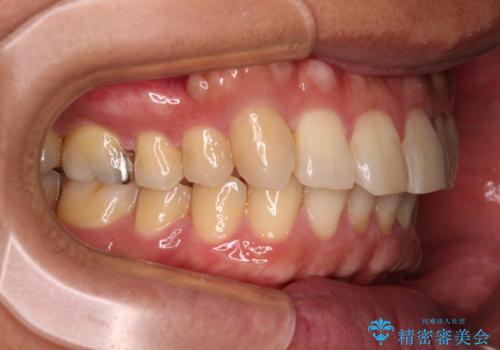

- 前歯のデコボコを気にして来院された患者様です。

配属異動や長時間勤務などによりインビザラインが十分に装着できない期間があり、インビザライン有効期限5年間ギリギリとなってしまいました。